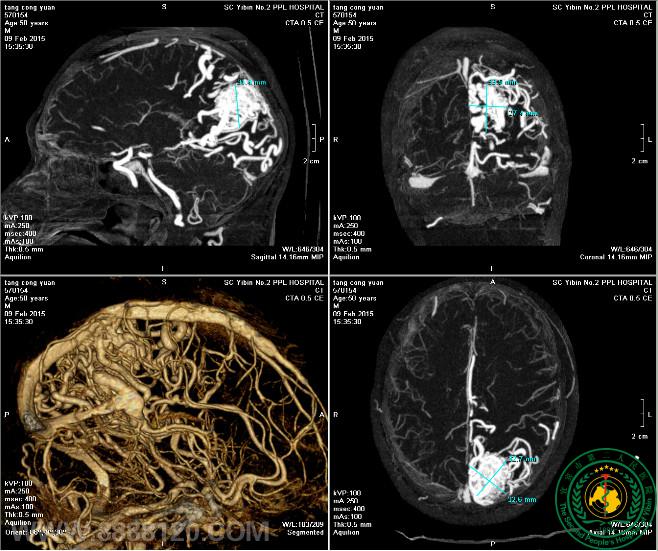

术前CTA:

我科成功完成1例复杂动静脉畸形介入治疗我科成功完成1例复杂动静脉畸形介入治疗